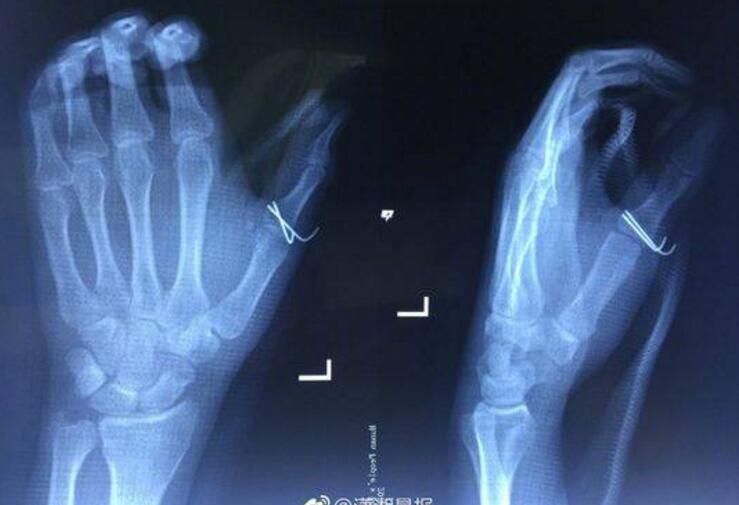

20岁的小袁是长沙某高校大三学生,7月29日晚餐前,小袁和往常一样,从出租房的冰箱里拿出一瓶可乐准备喝,结果不小心将塑料可乐瓶掉在地上。就在他捡起来打开瓶盖的瞬间,可乐瓶突然发生爆炸,将他的左手虎口处炸开一条约7cm长的口子。X光检查发现,小袁的左手拇指近节指骨骨折,需进行手术固定,于是将他收入创伤骨病科病房。